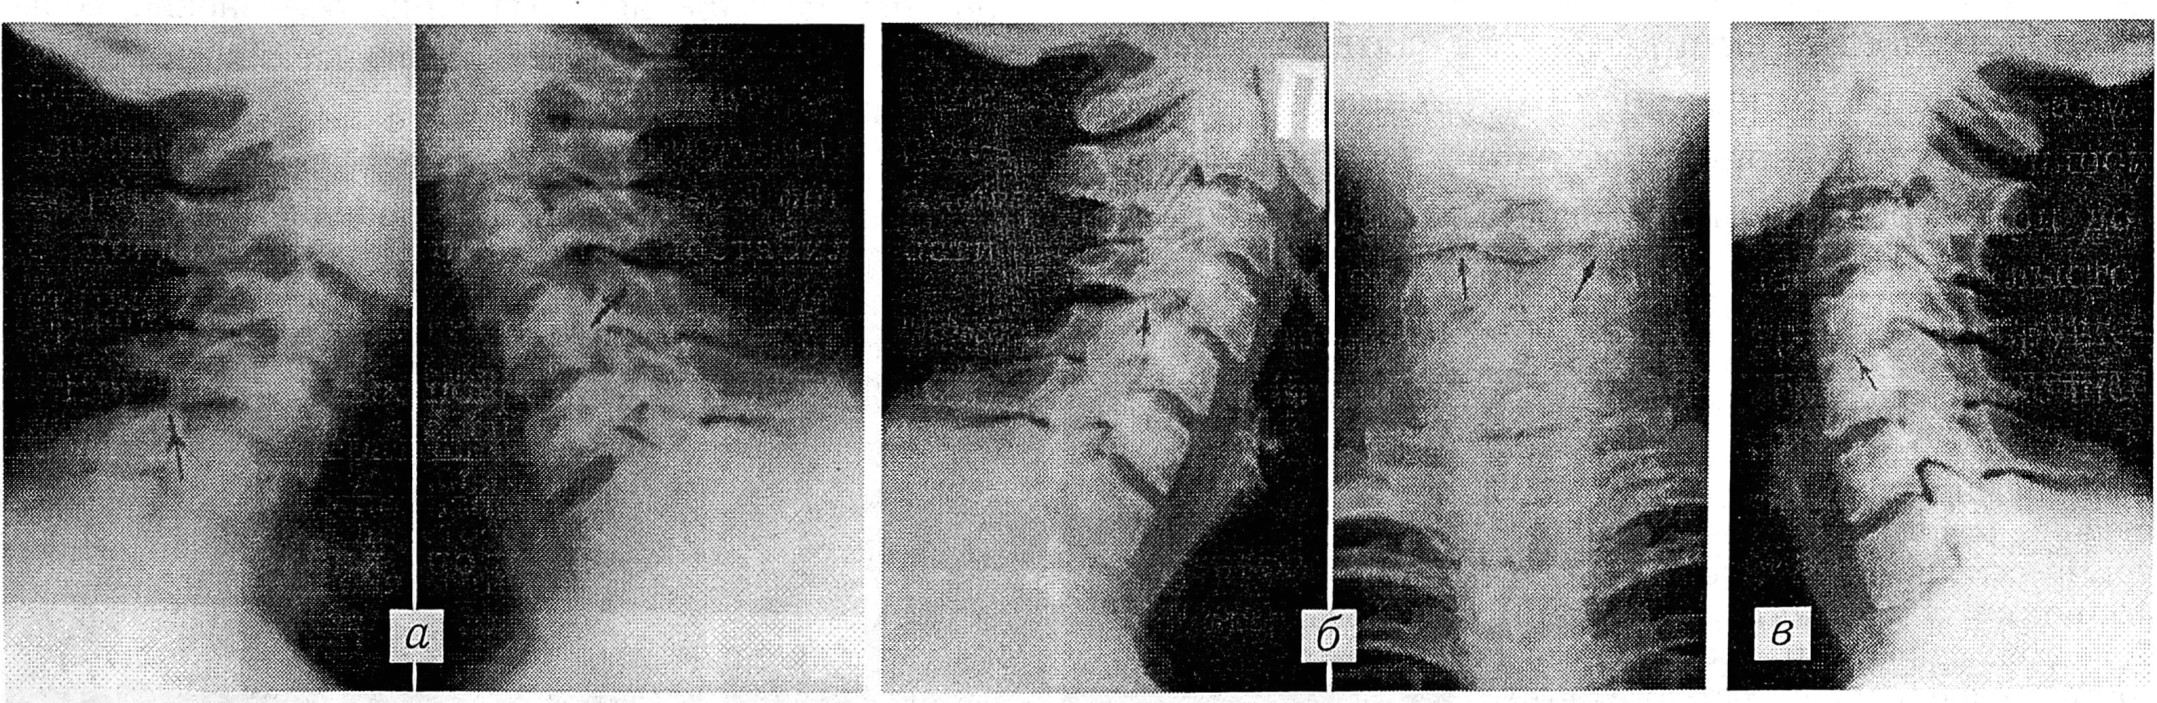

Больной 3.,26 лет, дома при погрузке мешка картошки резко повернул голову и почувствовал сильную боль в шее справа. Поступил в клинику через сутки с момента травмы. При осмотре голова несколько согнута, ротирована и наклонена влево. Мышцы шеи напряжены, больше справа. Наклон и ротация головы вправо болезненны и ограничены, влево более свободны. Пальпаторно определяется болезненность в проекции правых дугоотростчатых суставов С4 и С5 позвонков. Рентгенологически выявляется сглаженность шейного лордоза и несоответствие правых дугоотростчатых суставов С4 и С 5 на 1/3 суставных поверхностей. Передняя стенка позвоночного канала не деформирована (рис. 1, а). Диагностирован свежий правосторонний подвывих шейного отдела позвоночника на уровне С4 (ОСН-І). Проведено одномоментное устранение подвывиха с последующей иммобилизацией в положении гиперкоррекции клиновидным воротником Шанца в течение 5 нед. Больной вернулся к труду (милиционер) через 2,5 мес после травмы. При контрольном осмотре через 6 лет жалоб не предъявляет. Функциональные рентгенограммы свидетельствуют о стабильности позвоночно-двигательного сегмента С4—5 (рис. 1, б, в).

Рис. 1. Спондилограммы больного 3.

а — при поступлении: правосторонний свежий подвывих в шейном отделе позвоночника (С4), ОСН-І;

б, в — через 6 лет. (б — сгибание, в — разгибание): перемещение в дугоотростчатых суставах соответствует норме, признаки остеохондроза.